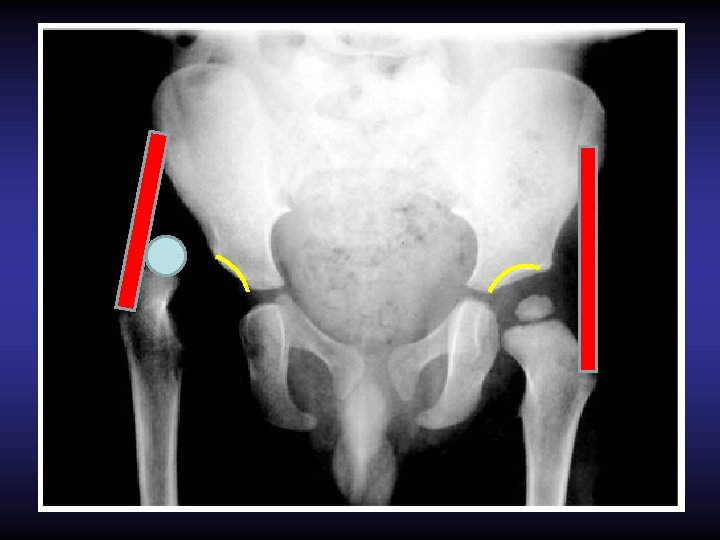

Radiographie